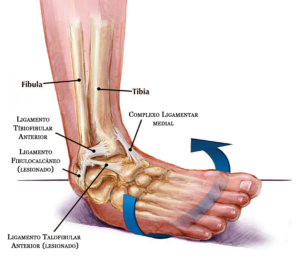

pé Fascite Plantar: Causas, Sintomas e Tratamentos Leia mais » abril 15, 2025 Geral 5 Fatos Essenciais Sobre a Panturrilha: Saúde, Função e Exercícios Leia mais » abril 15, 2025 joelho Artroscopia do Joelho Leia mais » março 27, 2025 Uncategorized Laser para joelho – Tratamento da Osteoartrite Leia mais » março 1, 2025 Geral Mialgia Tibial anterior: Não Confunda com Canelite: Leia mais » fevereiro 11, 2025 Uncategorized Fratura da Patela Leia mais » janeiro 29, 2025 Exercícios para Condromalácia nos Joelhos: Fortaleça com segurança Leia mais » janeiro 28, 2025 joelho Osgood-Schlatter: entendendo essa condição Leia mais » janeiro 27, 2025 Uncategorized Artrite Psoriática e inflamação articular Leia mais » janeiro 26, 2025 Tornozelo Torção do Tornozelo: Causas, Sintomas e Tratamentos Leia mais » janeiro 25, 2025 Tornozelo Tendinite Fibular: da causa ao tratamento Leia mais » janeiro 25, 2025 mão Síndrome do Túnel do Carpo Leia mais » janeiro 22, 2025 Geral Fêmur: O Maior e Mais Forte Osso do Corpo Leia mais » janeiro 16, 2025 Geral Tíbia: o principal osso da perna Leia mais » janeiro 16, 2025 Geral Luxação: O Que é, Causas, Sintomas e Tratamentos Leia mais » janeiro 7, 2025 Tornozelo Anatomia do Tornozelo: Ossos, Ligamentos e Tendões Leia mais » janeiro 3, 2025 Geral Clínica de Ortopedia em São Paulo Leia mais » dezembro 17, 2024 Uncategorized Dor Lateral no Joelho – 5 principais causas Leia mais » dezembro 17, 2024 Uncategorized Pubalgia: Causas, Sintomas e Tratamentos Leia mais » dezembro 16, 2024 Uncategorized Dor Atrás da Coxa: Principais Causas, Diagnóstico e Tratamento Leia mais » dezembro 13, 2024 Geral Bursite no Braço: Causas, Sintomas e Tratamento Leia mais » dezembro 11, 2024 Uncategorized Lombalgia Leia mais » dezembro 10, 2024 Uncategorized Cirurgia de Joanete: Quando Optar e Como Funciona Leia mais » dezembro 9, 2024 joelho Inflamação do Tendão Patelar: causas, sintomas e tratamento Leia mais » dezembro 6, 2024 joelho Bloqueio dos Nervos Geniculares no Joelho Leia mais » dezembro 3, 2024 joelho Hoffite: inflamação no joelho Leia mais » dezembro 2, 2024 joelho Dor no Joelho: as 15 principais causas Leia mais » dezembro 1, 2024 Geral Quadríceps: O Maior Grupo Muscular do Corpo Leia mais » novembro 27, 2024 Geral Panturrilha sentado e em pé Leia mais » novembro 27, 2024 joelho Cisto de Baker: Causas, Sintomas e Tratamentos Leia mais » novembro 18, 2024 Geral Osso: Estrutura, Funções e Saúde Leia mais » novembro 15, 2024 Ortopedia e Traumatologia Fratura Exposta: Entendendo as Fraturas Expostas de Fêmur e Tíbia Leia mais » novembro 15, 2024 Geral Canelite: Tudo o Que Você Precisa Saber Leia mais » novembro 11, 2024 joelho Infiltração no joelho Leia mais » novembro 11, 2024 coluna Nervo Ciático: tudo o que você precisa saber Leia mais » novembro 11, 2024 Geral Cãibras: Causas, Sintomas e Tratamentos Leia mais » novembro 10, 2024 Ortopedia e Traumatologia Especialista em Joelho Leia mais » novembro 5, 2024 Ortopedia e Traumatologia 4 bursites comuns: entenda e veja os tratamentos Leia mais » novembro 5, 2024 pé Metatarsalgia: dor na região anterior do pé Leia mais » outubro 30, 2024 Tornozelo Tornozelo Inchado: 7 Causas, Sintomas e Tratamentos Leia mais » outubro 28, 2024 Geral Mialgia: Causas, Sintomas e Tratamentos Leia mais » outubro 27, 2024 Geral Tendão de Aquiles: Função, Lesões e Tratamentos Leia mais » outubro 22, 2024 pé Anatomia dos Ossos do Pé: Estrutura e Função Leia mais » outubro 20, 2024 Ortopedia e Traumatologia Água no joelho (derrame articular) Leia mais » outubro 16, 2024 joelho O que é gonartrose ? Leia mais » outubro 16, 2024 cotovelo Epicondilite Lateral do Cotovelo: Causas, Sintomas e Tratamentos Leia mais » outubro 4, 2024 joelho Água no joelho (derrame articular) Leia mais » outubro 1, 2024 Geral Anti-inflamatórios: O Que São, Como Funcionam e Seus Usos na Ortopedia Leia mais » outubro 1, 2024 Geral O Que é Esporão: Causas, Sintomas, Diagnóstico e Tratamento Leia mais » outubro 1, 2024 quadril Bursite do Quadril: tudo o que você precisa saber Leia mais » setembro 18, 2024 Uncategorized O Que é Esporão no Pé? Causas, Sintomas e Tratamentos Leia mais » setembro 18, 2024 Geral Terapia por Ondas de Choque: O Que É, Como Funciona e Seus Benefícios Leia mais » setembro 17, 2024 joelho O que é gonartrose ? Leia mais » agosto 10, 2024 Geral Lesão Osteocondral: Diagnóstico, Tratamento e Reabilitação Leia mais » agosto 10, 2024 pé Dor no Pé: um queixa super frequente Leia mais » julho 13, 2024 joelho Problemas nos Joelhos: Causas, Sintomas e Tratamentos Leia mais » julho 7, 2024 Geral Ortopedia, entenda esta especialidade médica Leia mais » julho 5, 2024 joelho Joelho Estalando com dor, sem dor, é normal ? Leia mais » julho 5, 2024 BLOG – DICAS DE SAÚDE Leia mais » julho 2, 2024 Tornozelo Fratura por Estresse no Pé Leia mais » julho 1, 2024